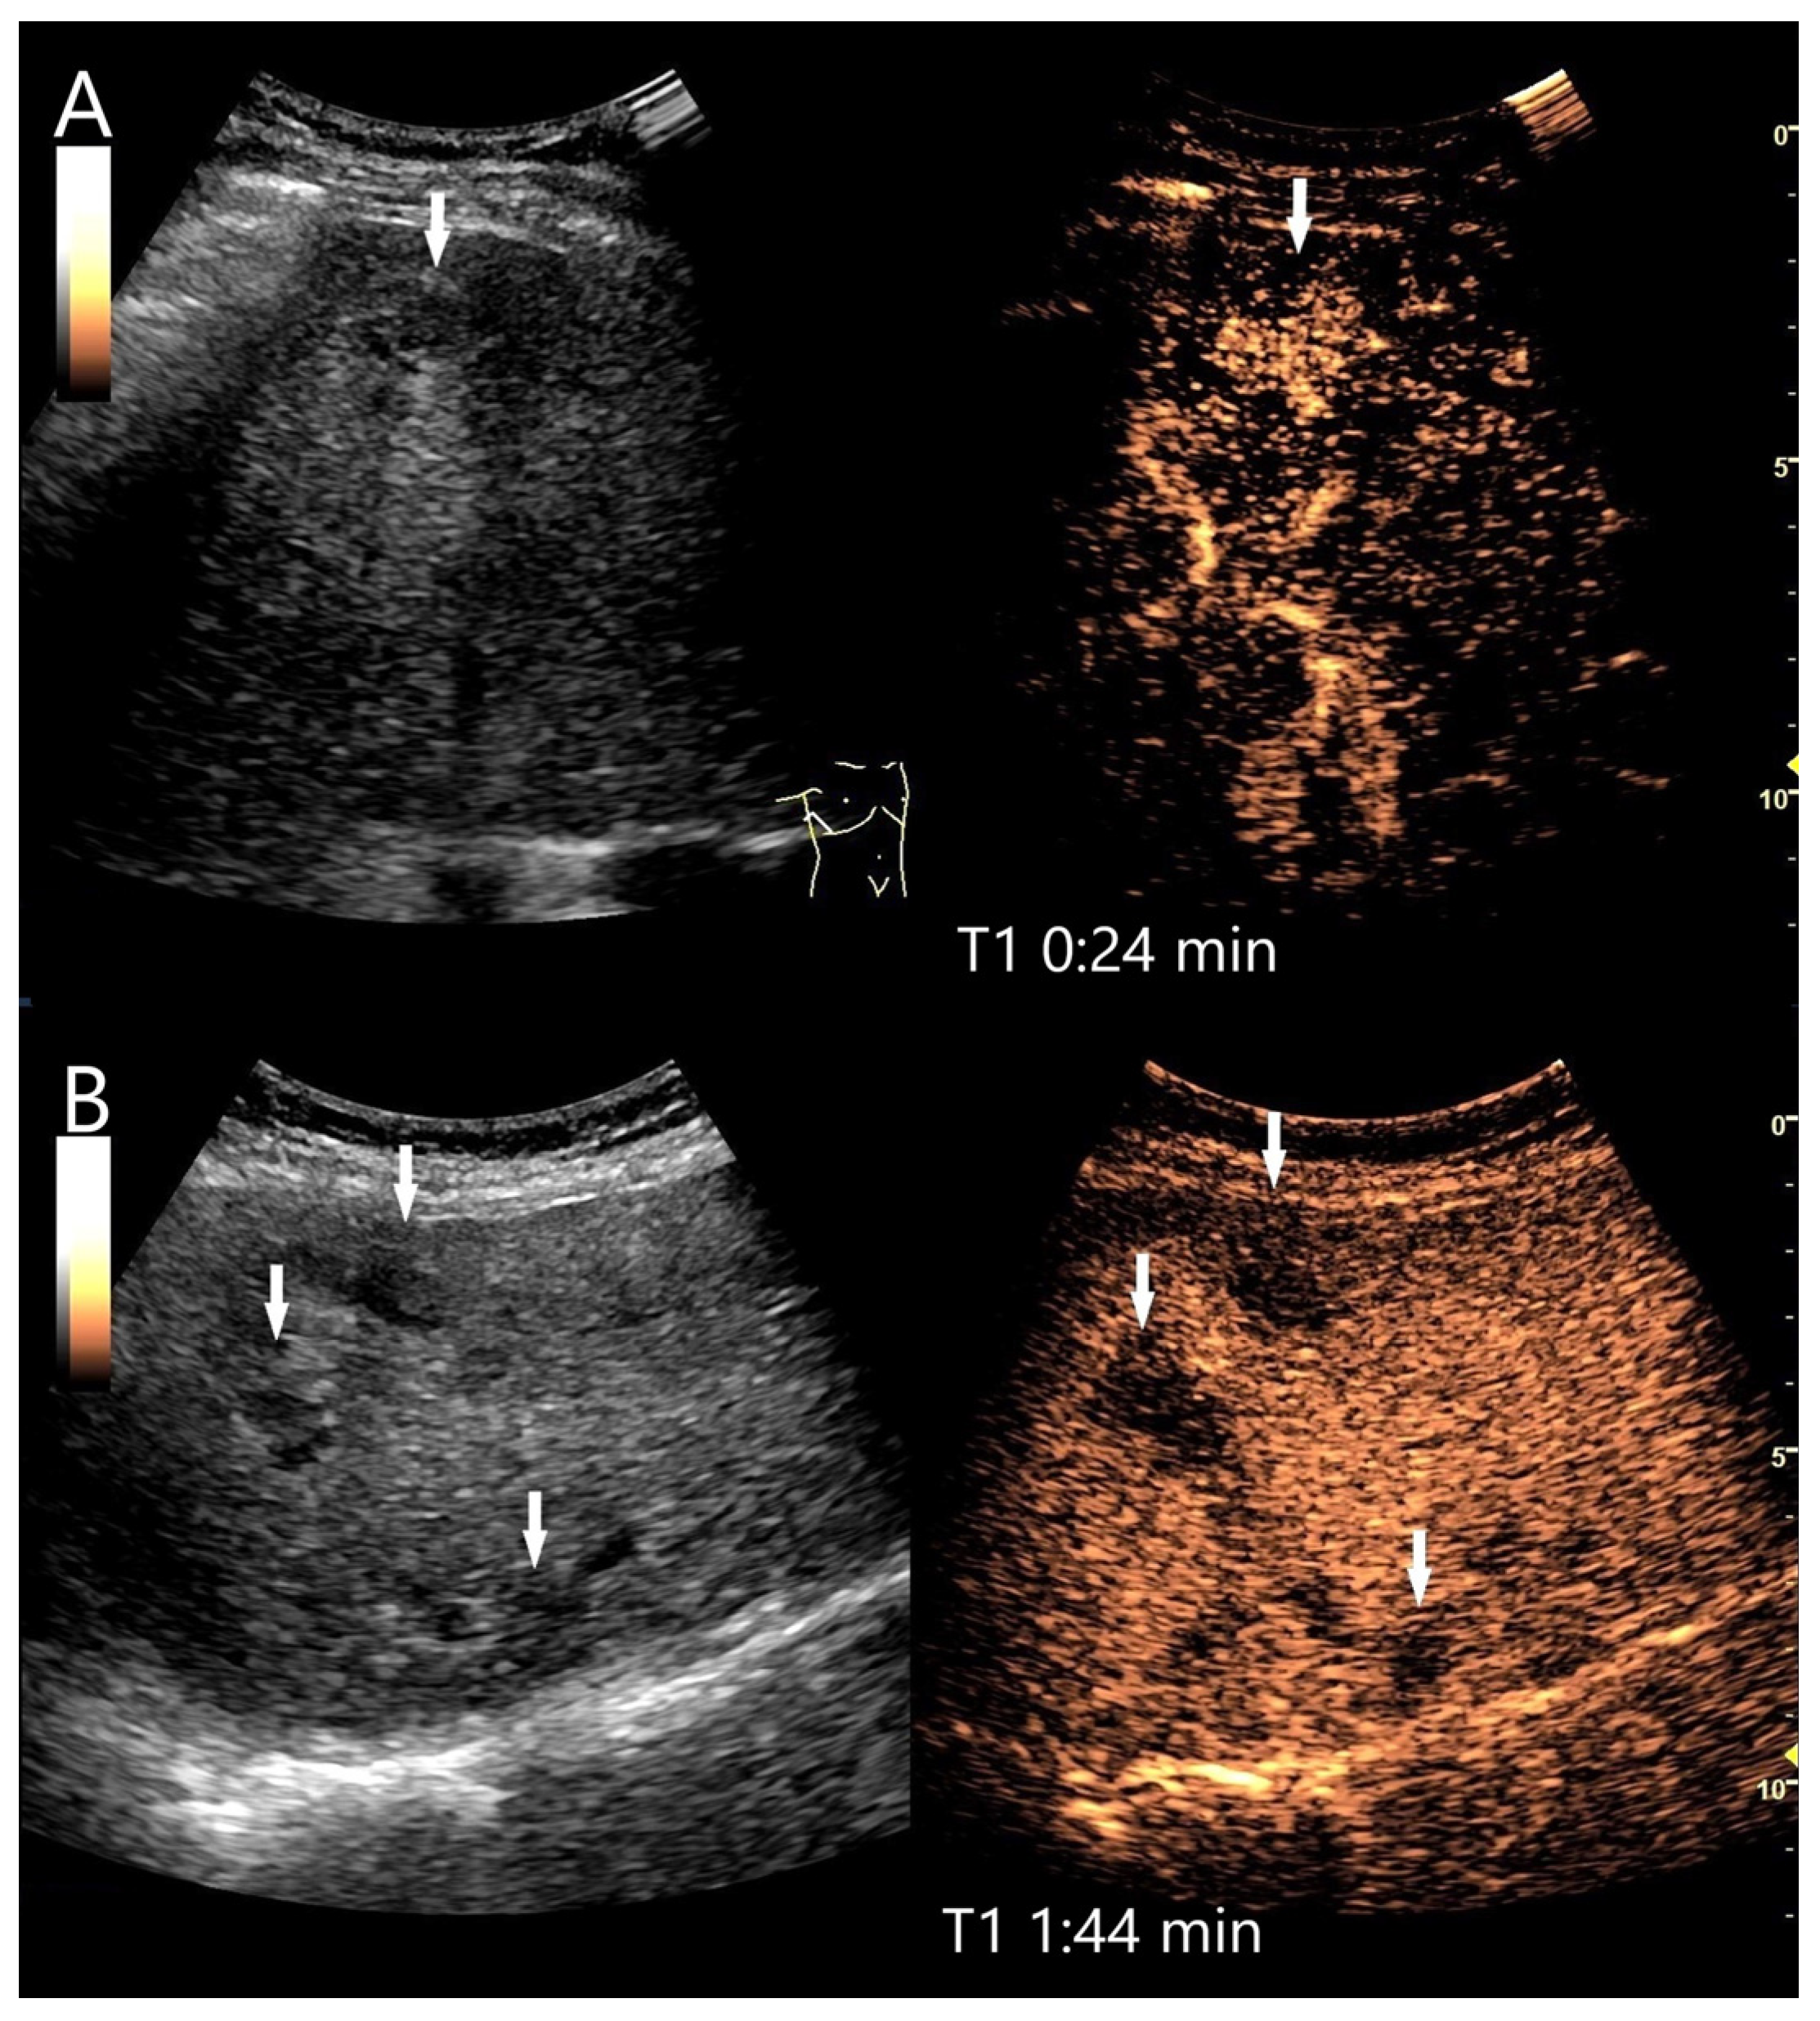

Sarcoidosis

Sarcoidosis is a complex granulomatous disease that can affect many organs, not just the lungs and lymph nodes [91]. Liver involvement is reported in up to 20% of patients. In micronodular changes, imaging shows no or only non-specific changes, such as hepatomegaly, hyperechoic parenchyma, and coarse nodular pattern. Rather rarely, focal hypoechoic lesions are detectable. There are only casuistic reports for sarcoidosis lesions in the liver. On CEUS, these hypoechoic lesions are characterized as differently arterially enhanced and progressive hypoenhanced lesions in the PVP and LP (Figure 13, Figure 14 and Figure 15). Persistent hyperenhancement is also described [91,92]. The progressive hypoenhancement can be a differential diagnostic aspect of malignancy. Completely non-enhancing (avascular) lesions in patients with long-standing sarcoidosis have also been described. Histologically, non-caseating granulomas were diagnosed [93]. Mediastinal lymphadenopathy, lung and spleen infiltrations can be diagnostically helpful. Splenic lesions in sarcoidosis behave similarly with progressive washout and hypoenhancement in the parenchymal phase of the spleen [94,95,96]. Histological confirmation by US or EUS-guided biopsy with detection of non-caseating granulomas is indicative. For differential diagnosis of granulomatous disease, see also the next subsection on tuberculosis.

Figure 13.

Hepatic sarcoidosis. Hepatosplenomegaly, up to 15 mm hypoechoic lesions in the liver and spleen, generalized lymphadenopathy, and poor general condition. On CEUS, these liver lesions are homogeneously hyperenhanced in the AP (arrow) (A). Washout with hypoenhancement develops from the PVP onwards (arrow) (B). Figure (A,B) show the CEUS image with the corresponding B-mode image in low MI mode. The diagnosis of the hepatic manifestation of sarcoidosis was made by US-guided biopsy of the liver.

Figure 14.

Sarcoidosis. Female patient with multiple hypoechoic liver lesions up to 10 mm. The CEUS shows after 25 s (A), 1 min (B), 2 min (C), and after 3 min (D) a progressive hypoenhancement. The US-guided biopsy revealed a diagnosis of hepatic sarcoidosis.

Figure 15.

Necrotizing sarcoid granulomatosis (NSG) (special form of sarcoidosis characterized by granulomatous vasculitis of the pulmonary veins and pulmonary arteries). Female patient. Multiple confluent hypoechoic focal FLLs (A). CEUS shows progressive hypoenhancement after 1 min (B), 2 min (C), and after 4 min (D). The US-guided biopsy revealed a diagnosis of liver involvement in NSG.